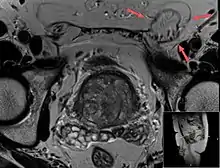

A physician may diagnose an inguinal hernia, as well as the type, from medical history and physical examination.[20] For confirmation or in uncertain cases, medical ultrasonography is the first choice of imaging, because it can both detect the hernia and evaluate its changes with for example pressure, standing and Valsalva maneuver.[21]

When assessed by ultrasound or cross sectional imaging with CT or MRI, the major differential in diagnosing indirect inguinal hernias is differentiation from spermatic cord lipomas, as both can contain only fat and extend along the inguinal canal into the scrotum.[22]

On axial CT, lipomas originate inferior or lateral to the cord, and are located inside the cremaster muscle, while inguinal hernias lie anteromedial to the cord and are not intramuscular. Large lipomas may appear nearly indistinguishable as the fat engulfs anatomic boundaries, but they do not change position with coughing or straining.[22]